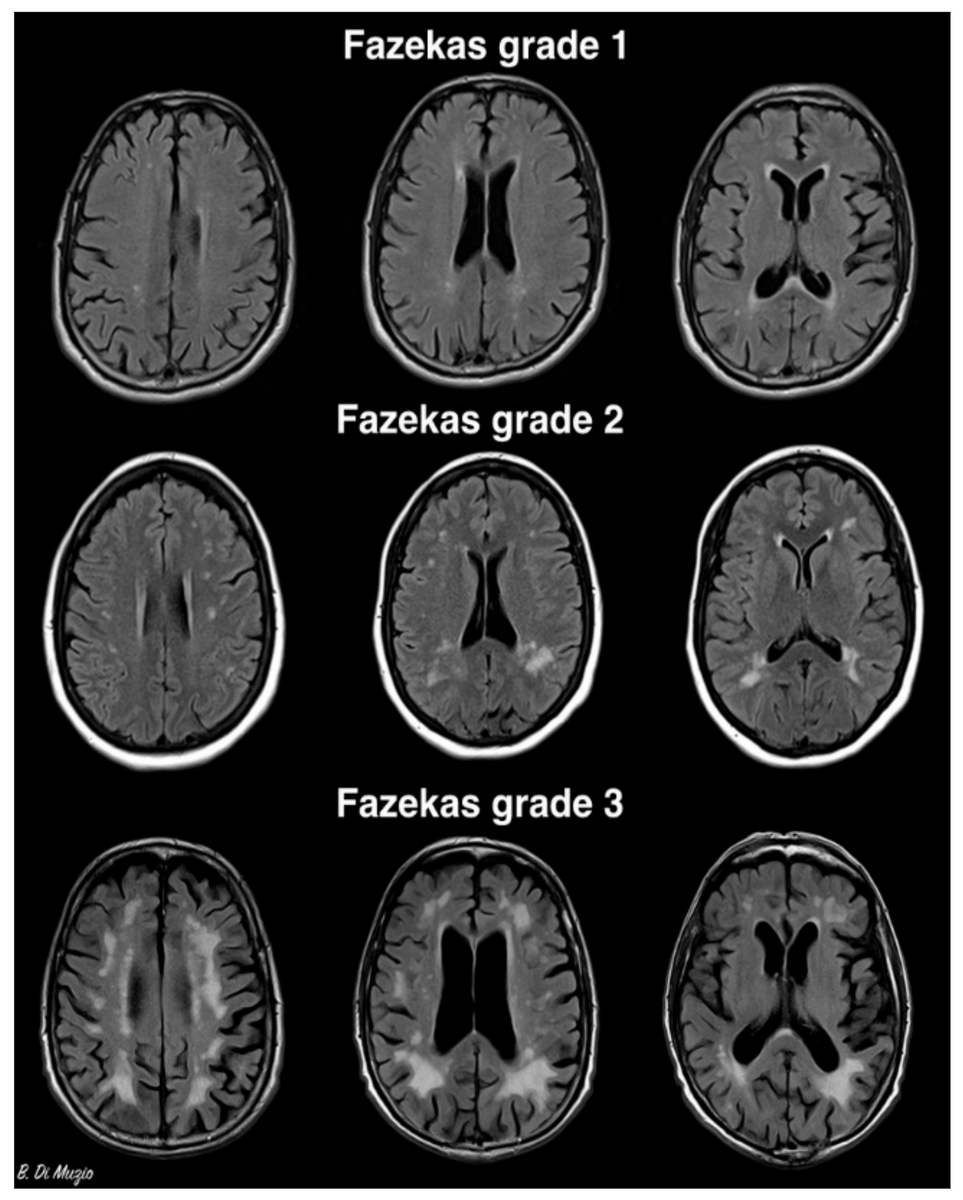

на вышеуказанных снимках МРТ сосудистые очаги- белого цвета